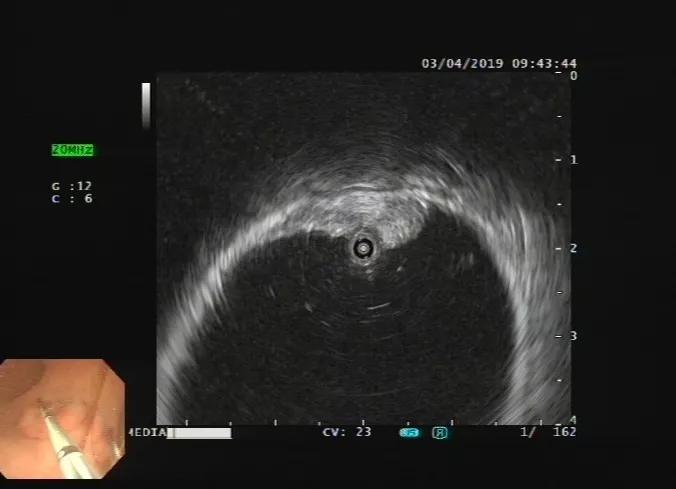

再比如我们做肠镜发现了肠腔肿瘤,也无法判断肿瘤侵润与多深?到了哪一层?

而超声内镜扫描观察就能简单判别:下图